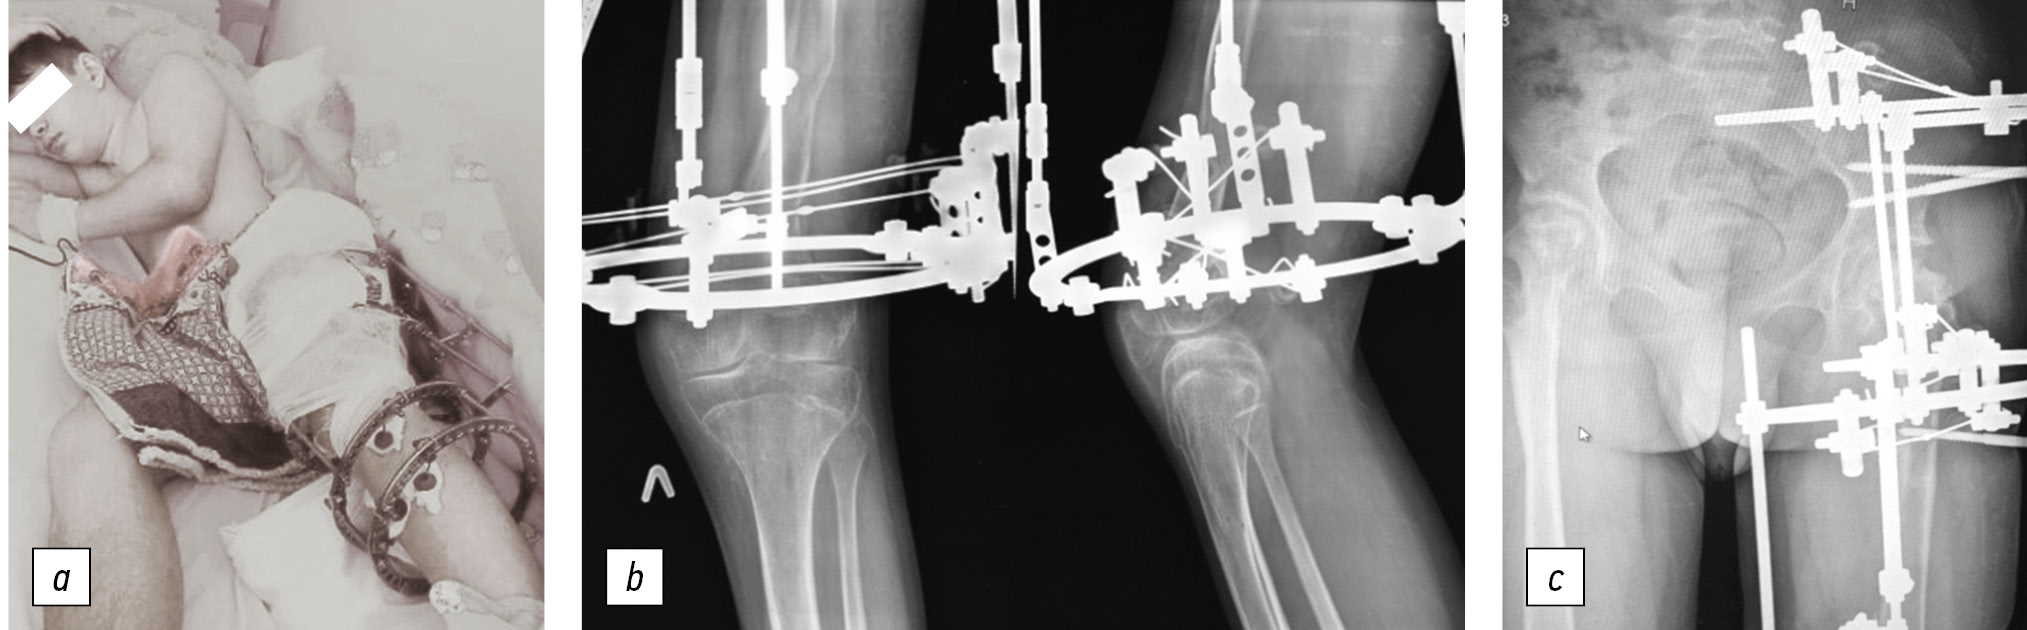

The child was admitted to the H.I. Turner National Medical Research Center for Сhildren’s Orthopedics and Trauma Surgery at the age of 6 years. He underwent surgical interventions to stabilize the hip joints, with an interval of 1.5 years. Therefore, in 2014 and 2015, hip arthroplasty was successively performed using demineralized bone and cartilage allografts. Concurrently, shortening detorsion osteotomies of the femoral bones were performed for joint decompression (Fig. 1).

Fig. 1. Appearance of the patient (a) and hip joint radiographs before (b) and at their surgical stabilization stages (c–e)